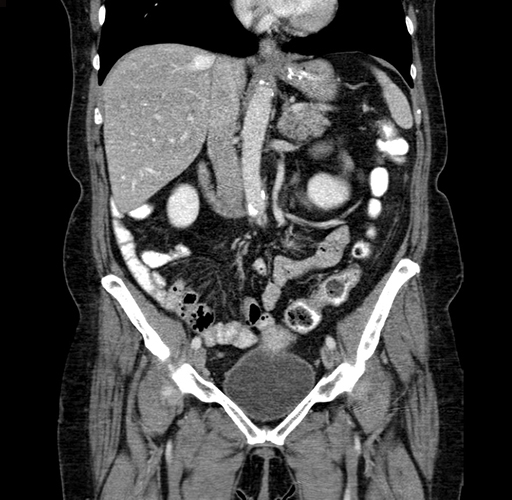

Pre-Chemo: Coronal Venous